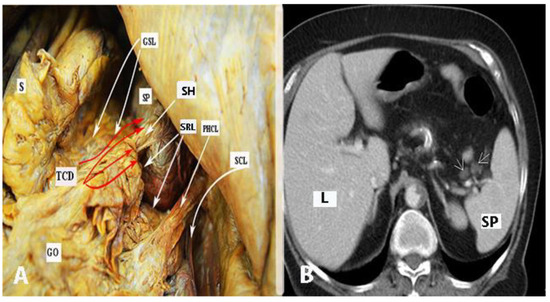

5. Hilum of the Spleen

Extraperitoneal Lymph Node Zones and Lymphadenectomy